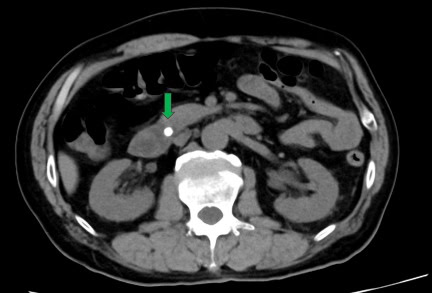

Ante el deterioro persistente, se inició hemodiafiltración continua por acidosis metabólica y fallo renal. Una nueva TC abdominal mostró ascitis leve (acumulación anormal de líquido en el abdomen) sin pseudoquistes pancreáticos.

FIGURA 2: TAC abdominal al ingreso del hospital que muestra ascitis de nueva aparición (flecha verde) sin evidencia de pseudoquiste pancreático. Foto: Caso Clínico - Kobori et al.